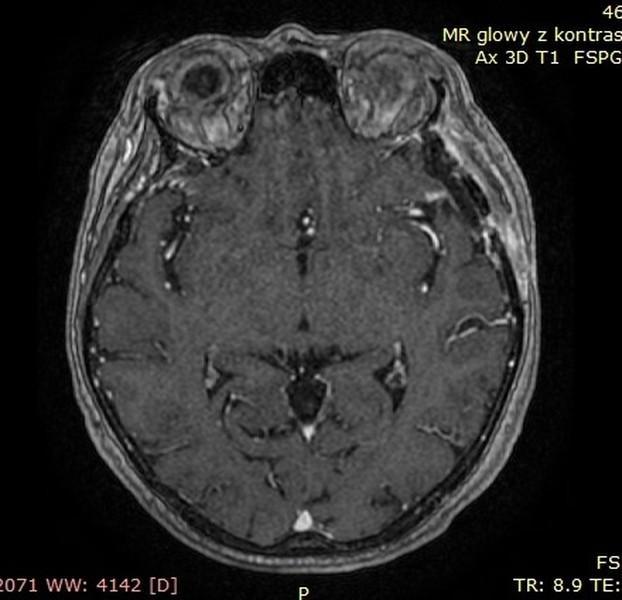

OPONIAKI DUŻYCH ROZMIARÓW I OPONIAKI OLBRZYMIE

Od wielu lat zajmuję się chirurgią oponiaków wewnątrzczaszkowych o różnych lokalizacjach oraz rozmiarach. W grupie operowanych przypadków znalazły się także oponiaki dużych rozmiarów i oponiaki olbrzymie. Guzy te potrafią rosnąć powoli. Wielokrotnie objawy kliniczne przez wiele lat są niespecyficzne - tylko bóle głowy!!! Początkiem przyspieszonej diagnostyki bywa pierwszy w życiu napad padaczkowy. Tak było w grupie prezentowanych przypadków dużych/olbrzymich oponiaków. Wiele z tych guzów pomimo swojej naturalnej łagodności stanowi poważne wyzwanie operacyjne. Operacja oponiaka – to działanie operacyjne wobec guza rosnącego zewnątrzmózgowo, wielogodzinne spokojne oddzielanie i usuwanie „żeby mózg o tym nie wiedział”

Poniżej przedstawiono grupę operowanych pacjentów.

Pacjent pierwszy - Guz usunięty całkowicie, guz łagodny. Pacjent w stanie dobrym, bez objawów neurologicznych – wypisany do domu.

Przed operacją

Tak jak napisałem guzy - oponiaki potrafią rosnąć powoli nie dając żadnych objawów, mózg dostosowuje się do utraty rezerwy wewnątrzczaszkowej dlatego, że proces przebiega powoli. Początkowym objawem był pierwszy w życiu napad padaczkowy. Potem diagnostyka – rezonans magnetyczny i operacja oponiaka. Działanie operacyjne wobec guza rosnącego zewnątrzmózgowo, wielogodzinne spokojne oddzielanie i usuwanie „żeby mózg o tym nie wiedział”

Poniżej prezentacja badan diagnostycznych:

• Ryc 1-7 – badania diagnostyczne przedoperacyjne,

• Ryc 8-13 – badania po operacji.

Pacjentka przyjęta nieprzytomna po napadzie padaczkowym – podczas operacji guz został usunięty całkowicie, miał charakter łagodny. Pacjentka w stanie dobrym, bez objawów neurologicznych – wypisana do domu.